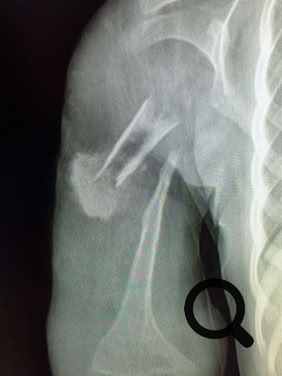

In the print version of the book there are many black and white images. The full colour versions are found in the gallery below. Depending on your connection performance the enlarged images may take a little time to load.